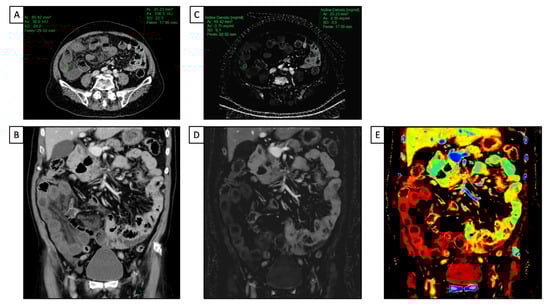

Even if MRI is considered the gold standard in evaluating small intestine inflammatory bowel diseases [Maaser2019], DECT has proven to have high diagnostic accuracy in assessing inflammation activity and severity in those with Crohn’s disease [49,50,51] (Figure 4).

Figure 4.

A 66 y-o male with diffuse abdominal pain underwent abdominal CT with a final diagnosis of distal ileum bowel ischemia. (A,C) Axial and coronal conventional CT images acquired after intravenous contrast media injection show a slight difference in attenuation value (HU) of the small bowel walls, with reduced enhancement in the distal ileum and regular enhancement in jejunum and proximal ileum; (B,D) iodine maps clearly show the difference in iodine uptake between the normal walls of the jejunum and proximal ileum and the poor iodine uptake of the distal tract of the ileum; (E) the Z-effective map allows us to better and more simply define the different enhancement in terms of colors between healthy and ischemic bowels due to the atomic number of iodine.

In particular, it has been demonstrated that a quantitative assessment of DECT parameters, including NIC and slope of the HU curve (which represents the X-ray attenuation coefficient at different energy levels), had higher accuracy in predicting intestinal activity and severity in ileocolonic Crohn’s disease when compared to conventional SECT parameters [49]. Further investigations corroborated these results and proved that the walls of the bowel segments with active inflammation show a higher NIC value than those without inflammation, using histopathologic results from either ileocolonic resection or biopsy of the terminal ileum as the reference standard [51].

With regard to detector-based platforms, Kim et al. evaluated various qualitative and quantitative dl-DECT features in a population of thirty-nine patients with Crohn’s disease at different stages, ranging from remission to severe activity state. Due to its ability to quantify the contrast distribution across intestine walls at a single point in time, the iodine concentration measured on the iodine map was the only independent variable associated with the Crohn’s disease activity index [52]. Active disease qualitative assessment may also be improved because of the increased hyper-enhancement seen in low-keV images. Lee et al. demonstrated that low-energy (40 keV) VMIs on a dl-DECT scan provided the best CNR for both healthy and pathologic small bowel walls. Moreover, the diagnostic performance in assessing active Crohn’s disease of three radiologists with different levels of experience was significantly improved with the addition of low-energy VMIs, compared to only the conventional PEI at 120 kVp [53].